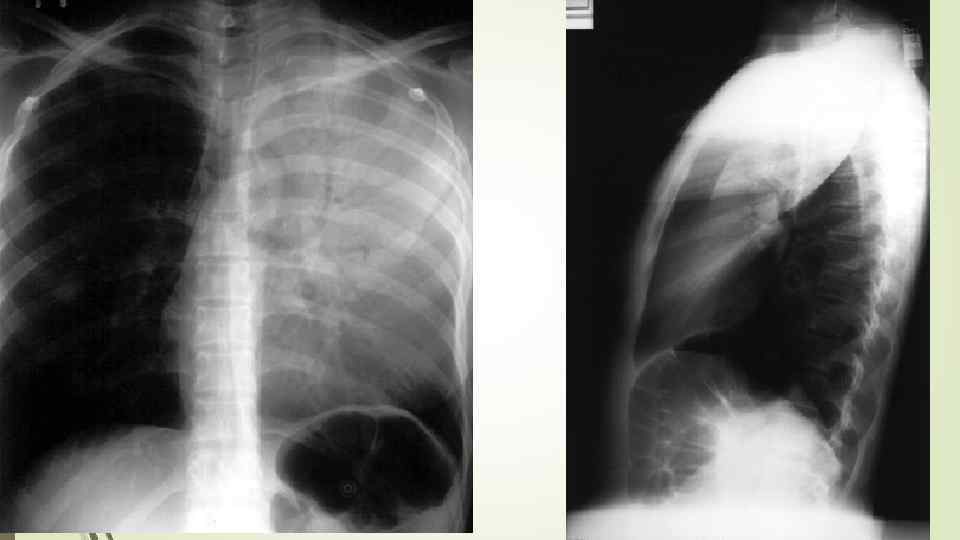

Дифференциальный диагноз ателектаз инфаркт легкого туберкулезная пневмония

Дифференциальный диагноз ателектаз инфаркт легкого туберкулезная пневмония

Исходы крупозной пневмонии Благоприятные: полностью рассасывается, структура легких восстанавливается. Неблагоприятные исходы: - нагноение инфильтрата с развитием абсцедирующей пневмонии, иногда с прорывом в плевральную полость и образованием пневмоторакса; - переход в хроническую форму с последующим развитием бронхоэктазов, цирроза, иногда карнификации.

Исходы крупозной пневмонии Благоприятные: полностью рассасывается, структура легких восстанавливается. Неблагоприятные исходы: - нагноение инфильтрата с развитием абсцедирующей пневмонии, иногда с прорывом в плевральную полость и образованием пневмоторакса; - переход в хроническую форму с последующим развитием бронхоэктазов, цирроза, иногда карнификации.